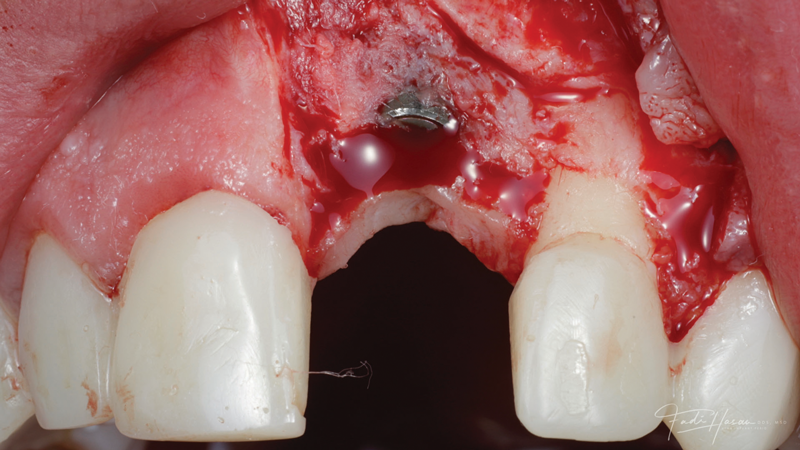

(12.) Flap reflection to assess the position of the coronal aspect of the implant and facilitate soft-tissue grafting.

Figure 12